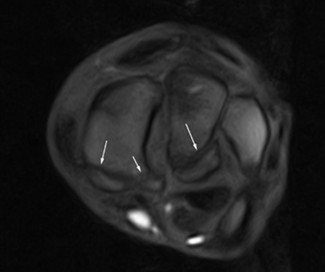

Carpal or tarsal bone fractures

Fractures of the carpal (image 2 and 3) or tarsal bones (image 4) are not always straightforward to diagnose with radiographs alone. MRI may safely – in a standing patient – provide an accurate diagnosis, precise fracture configuration, as well as assessing potential soft tissue injuries. This can be used for surgical planning of the fracture repair, or if conservative treatment is opted for, MRI is very useful for monitoring the fracture healing (Zimmermann et al. 2023).

MRI can further assess the position of these fracture fragments in association with the carpal sheath, which is located directly palmar to the fracture fragments.